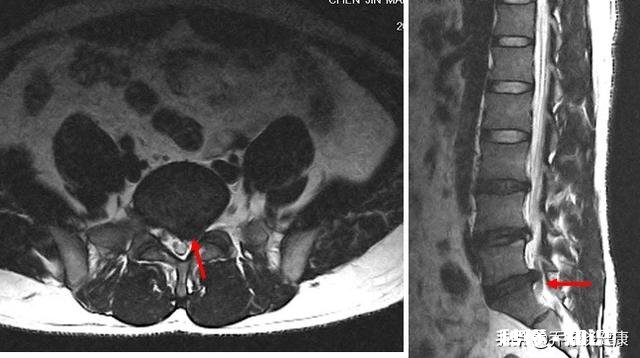

腰椎间盘突出

对于腰椎间盘突出来讲,引起症状的原因主要是硬膜囊和神经根受到刺激诱发的,突出的部位是髓核,造成压迫的是髓核和部分纤维环,骨头本身没有大的变化,腰椎小关节紊乱可能发生,也可能不发生!

【正骨对腰椎间盘突出有效果吗是什么原理呢】正骨,实际上对于腰段脊柱来讲,主要矫正的是腰椎小关节紊乱,腰椎的活动是和腰椎关节突关节位置息息相关的,一旦位置发生非正常范围内改变,这个时候引起滑膜嵌顿就会造成相应的症状,归位的时候会有“咔”的声音,矫正之后立马轻松!

正骨不对应从这方面看,腰椎间盘突出,髓核出来了,那么掰来掰去“咔咔响”这是不对应的处理方式,髓核是胶冻样物质,正骨显然不会让它回去,且那种旋转的剪切力正骨,如果做不好,可能进一步损伤椎间盘加重症状 。